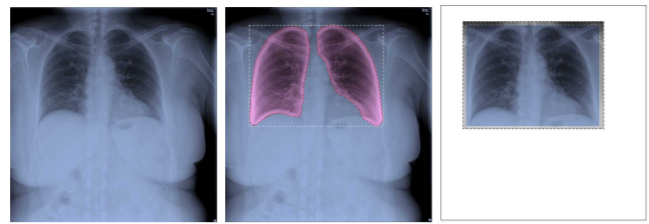

A. Segmentation - Based Cropping

CXR을 찍을 때 장비 브랜드가 다르면 장비가 찍는 신체의 영역도 달라지는 모양이다..! 어떤 거는 어깨까지 찍어버리고 어떤 거는 그것보다 더 넓게 찍어버리고 뭐 이런식.

그래서 인풋 이미지가 서로 다른 신체의 영역을 잡아버린다면 이 역시 모델 성능에 영향을 줄 수 있기 때문에 이를 사전에 방지하기 위해서 lung 만 segment 하여 input으로 넣어준다.

이때 이용한 것은 U-Net segmentation 이며, TuberCulosis Chest X-ray Image Dataset과 RSNA Pneumonia CXR challenge dataset 을 이용해서 사전 학습을 시켰다고 한다.

segment 된 좌우 폐가 모두 담길 수 있는 가장 작은 rectangle로 이미지를 잘랐다고 한다.

그리고 혹시 모르니 segment 한 이미지에서 좌우 상하로 2.5 픽셀씩 더해줘서 필요한 정보의 손실을 막고자 했다고 한다.

Figure 3